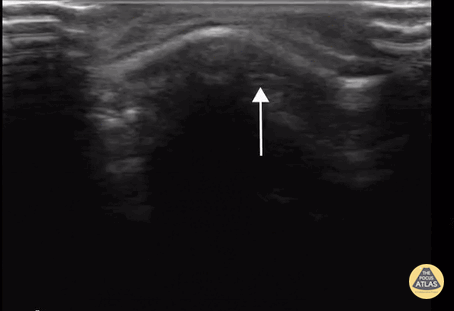

11 month old with depressed frontal ping pong fracture. These fractures occur when the bone is soft enough to indent rather than outright break. Contributor: Antonio Riera, MD